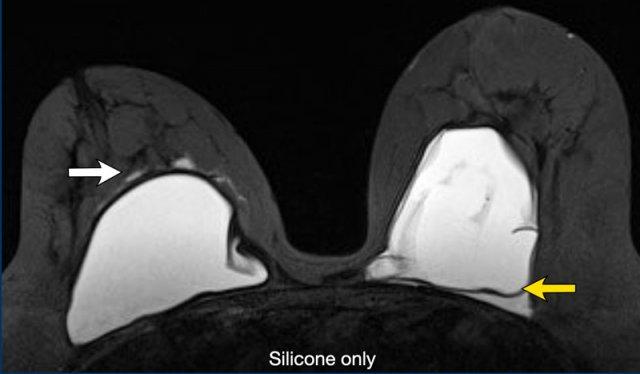

Vỡ túi ngoài bao xơ

Bệnh nhân nữ này có vỡ túi ngoài bao xơ bên phải với silicone nằm ngoài bao xơ dày (mũi tên trắng).

Ở vú trái có vỡ túi trong bao xơ được biểu hiện bằng đường dưới bao xơ với silicone ở cả hai phía của đường này (mũi tên vàng).